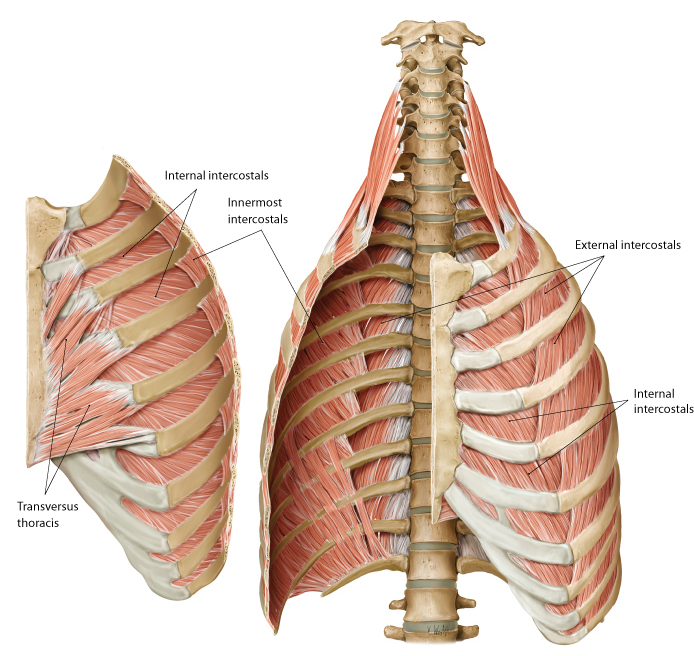

identify the actions of these muscles and their relationship to each other in space?

- External intercostals (E)

- Internal intercostals (I)

- Innermost intercostals (IM)

External intercostals (E)...inspiration...most superficial

Internal intercostals (I)...expiration

Innermost intercostals (IM)...elevate?…not completely understood...most deep

what is between the internal intercostals and the innermost intercostals? which muscle is on top?

when looking at a picture how do you identify these muscles, what should you look for?

BV's and nerves in between them

internal intercostal on top

basically, look for the innermost muscle and if its muscle colored it is the innermost intercostals...if it looks like a layer was peeled and you see nerves traveling horizontal, it indicates that you are looking at the internal intercostals

action and location of the:

transversus thoracis?

subcostal muscles?

Transversus thoracis (TT) (in front)...expiration (depress

ribs)...located on internal anterior thoracic cage...in 1st

picure

Subcostal (SC) muscles (in back and on

inside)...inspiration (elevate ribs)...located on internal posterior

thoracic cage (in second picture they are the strips going up)